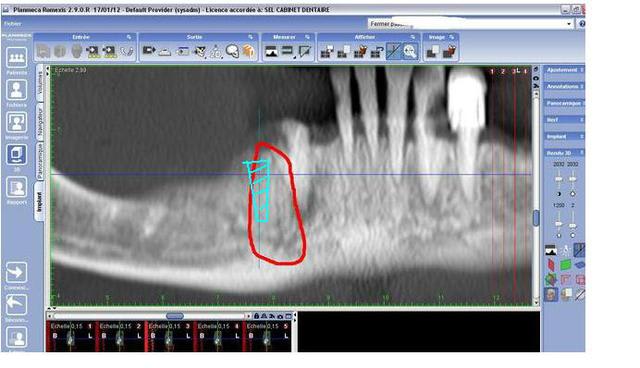

Pensez vous que cette continuité du nerf sera genant pour la pose d'un implant (trait violet) en terme de forage (je ne pense pas ), mais surtout en terme de sensibilité post-op

c'est pas le pedicule incisif qui inquiete docj, mais cette image qui ressemble à une branche du ndi et qui remonterait parralellement a la canine.

Oui, mais en vertical, en distal de la canine, qui remonte?C' est pas le canal incisif qui se serait trompé de route!

Oui effectivement. Je parle de ce qui remonte en vertical en arrière de la canine. Merci

"En ce qui concerne ta question initiale, je ne peux pas vraiment te dire ce qu'il ce passera si tu touches ce rameau nerveux, ou même si tu le frôles juste. Par contre , il me semble réalisable de positionner l'implant de sorte de rester a distance du problème, tel que je l'ai dessiné sur ton image fourni en pièce jointe. il va de soi que, n'ayant pas de plan de traitement, je ne peux qu'estimer la position de l'implant en 44."